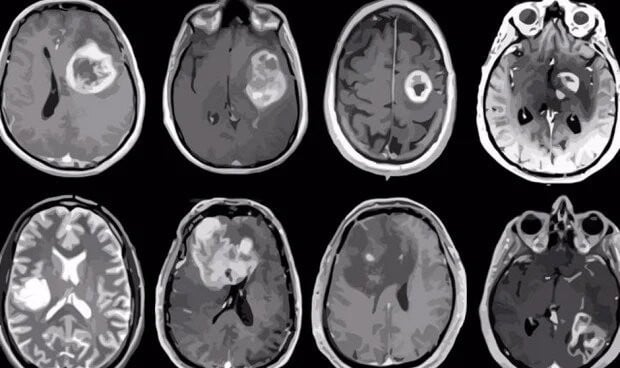

Aunque estas terapias son eficaces contra cánceres sanguíneos como la leucemia y el linfoma, los cánceres que producen tumores sólidos siguen siendo difíciles de tratar con inmunoterapias CAR-T, ha explicado David Kranz, director del estudio y profesor emérito de Bioquímica en Illinois. "No hay el mismo tipo de dianas para estos receptores en los tumores sólidos que en los cánceres de la sangre, y es muy difícil encontrar una diana que no se encuentre también en los tejidos sanos. El otro factor es que las células tumorales sólidas tienen su propia forma de suprimir la respuesta inmunitaria para eludir el reconocimiento de las células T y otras células inmunitarias. Se está trabajando mucho para intentar superar esas dos barreras: encontrar buenas dianas y encontrar el tipo adecuado de CAR que puedan reconocer esas dianas", ha subrayado Kranz.

En el nuevo estudio, los investigadores se centraron en un carbohidrato que se encuentra en la superficie de las células tumorales sólidas, pero no de las células sanas. Desarrollaron moléculas CAR con distinta afinidad por la molécula y las probaron primero en cultivos de células de cáncer de ovario y luego en ratones vivos con tumores de cáncer de ovario.

Descubrieron que los receptores con mayor afinidad por el carbohidrato eran muy eficaces para ayudar a las células T a encontrar y destruir el cáncer, reduciendo o eliminando los tumores tras una sola dosis intravenosa o inyectada, y que seguían actuando durante meses o incluso más de un año después de la dosis inicial, alargando la vida de los ratones.